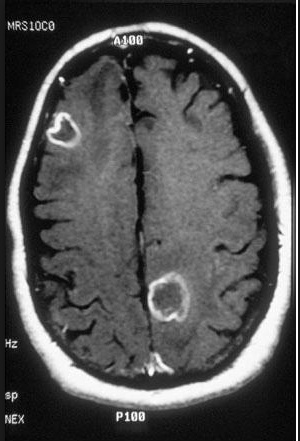

extra lenses: Brain abscesses. Multiple ring enhancing lesions on CT or MRI

red: turban: Encephalitis

ping sticking out turban: Brain biopsy to differentiate from CNS lymphoma